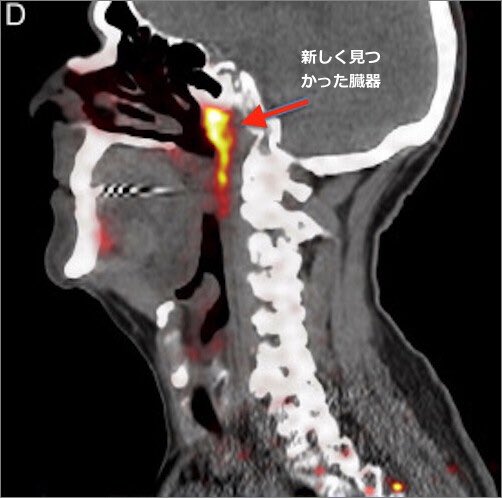

偶然ですか? PCR検査のメソッドは、人間の鼻の奥で発見された「新しい臓器(尿細管唾液腺)」 を直撃している。 twitter.com/Junika2022/sta…